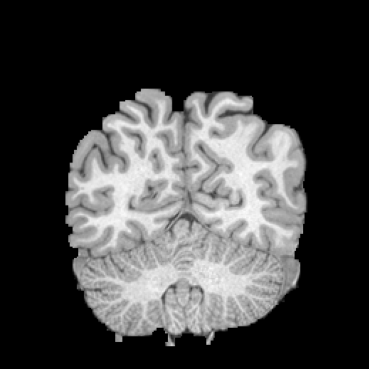

HCP Brain MRI We train on 1076 brain-extracted T1w images from the HCP dataset [24] and test on a sample of 100 pairs between 36 images via mean Dice over 28 midbrain structures [20, 21]. We train and execute the network at [130155130], then compute the Dice score at full resolution.

OASIS Brain MRI We use the OASIS-1 [12] data preprocessed by [9]. This dataset contains images of 414 subjects. Following the data split in [14], we train on 255 images and test on 153 images555Due to changes in the OASIS-1 data, our test set slightly differs from [14]. We evaluate all methods using our testing protocol so that results are consistent.The images in the dataset are of size [160192224], and we crop the center of the image according to the preprocessing in [14], leading to a size of [160144192]. During training, we sample image pairs randomly from the train set. For evaluation, we randomly pick 5 cases as the fixed images and register all the remaining 148 cases to the 5 cases, resulting in 740 image pairs overall.